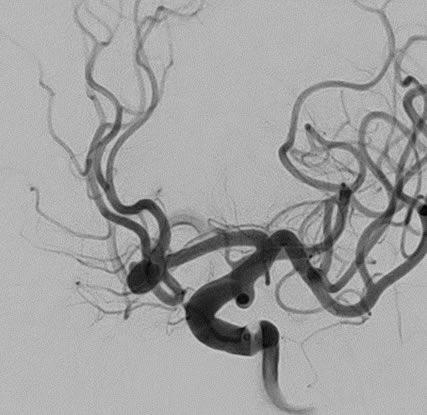

<症例② 脳動脈瘤 コイル塞栓術>

血管撮影検査を行うにあたり、カテーテルと呼ばれる細い管を血管内に挿入します。カテーテルを目的の血管までガイドワイヤーを用いて誘導し、カテーテルから造影剤を注入して、目的の血管を撮影します。

また、病変部が確認されたら、ステント留置術、血栓吸引術、コイル塞栓術などを行うことにより、病変部を治療することも可能です。